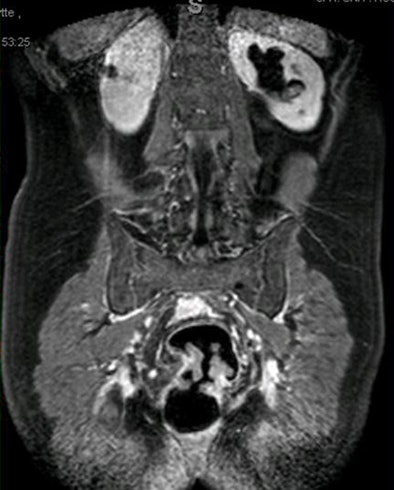

| The researchers analyzed regions of interest in an artery, the tumor overall, and the tumor region with the highest signal for maximum relative enhancement, time to peak, wash-in and wash-out. Both readers found that only the differences in wash-in values in the high-intensity area and the total tumor region for both patient groups (benign and malignant) were significantly different (above). Interobserver agreement was high (below). |

Two experienced radiologists evaluated the images, assessing regions of interest in an artery, a tumor region representative of the tumor as a whole, and a tumor region with the highest signal, Achiam said. The regions of interest were analyzed for maximum relative enhancement, time to peak, wash-in, and wash-out. The researchers measured interobserver correlation (observer I versus observer II) and observer reproducibility (for observer I).

"We unfortunately only had seven benign tumor stenoses, but the results I think were excellent," he said. "We found that only the wash-in time and the washout time were significantly different between benign and malignant tumors [p < 0.01]."